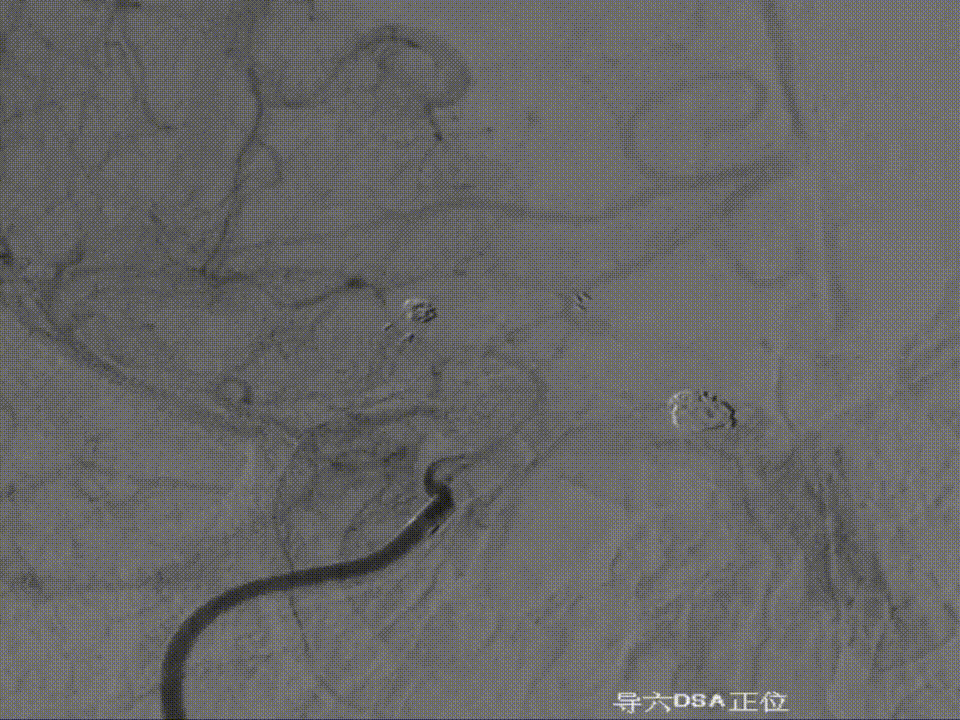

撤出弹簧圈,Asahi 0.014微导丝引导璞慧 0.017微导管穿支架网孔进入动脉瘤内。

继续填入Target 1.5/2弹簧圈成篮,后完全释放支架,其近端位于颈内动脉分叉处,远端位于A1远端。

填入第一枚弹簧圈

通过调整栓塞微导管的张力继续填入Target 1/3弹簧圈。

术后正侧位造影:Raymond Ⅲ级